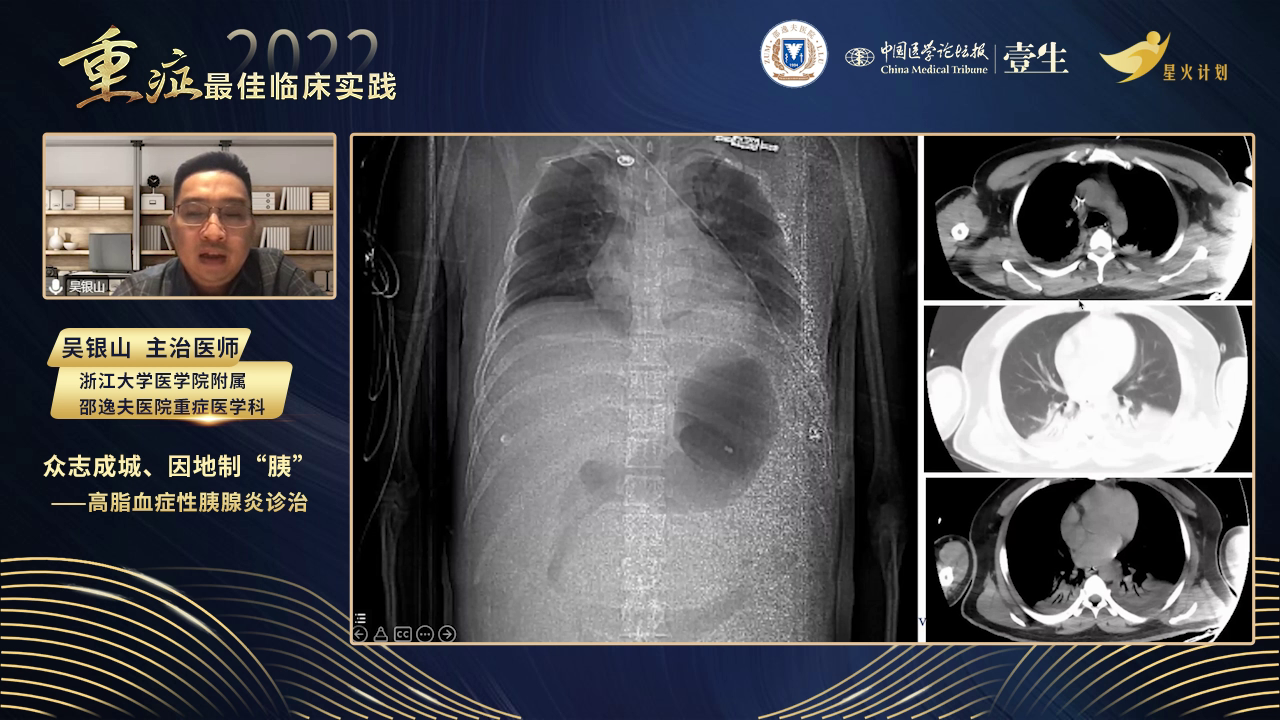

患者为28岁男性,因上腹痛五天于2021年8月7日入院。

此次发病,上腹痛逐渐加重,于绍兴中心医院就诊,检查显示淀粉酶、血糖、甘油三酯等多项指标异常,CT提示胰腺炎等病变,给予对症支持治疗。随后腹胀加重,出现下肢麻木、尿量减少等症状,转至当地医院ICU,进行气管插管、血浆置换等治疗。因病情危重,测腹内压32cmH2O(23.5mmHg),于发病第六天转至浙江大学医学院附属邵逸夫医院。

根据患者症状、体征及检查结果,依据胰腺炎诊断标准,该患者符合重症急性胰腺炎诊断。其分型为高脂血症型,合并胰腺局部并发症、腹腔间隔室综合征及多脏器功能不全,同时存在脂肪肝、右肾结石等情况。胰腺炎分级采用2012年亚特兰大标准,分为轻症、中重症和重症,脏器功能衰竭评估通过改良Marshall评分动态进行,需注意各系统独立评分,任一器官评分≥2分提示脏器功能衰竭。